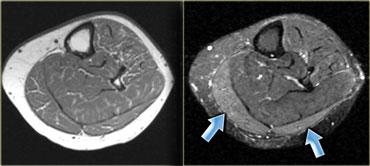

Fascial hernia

Rách cân cơ biểu hiện như một khối u, tín hiệu thường bình thường (tương tự như một cơ phụ).

Cơ thoát vị qua chỗ khuyết cân cơ, lồi ra khi cơ co lại.

Đây là khối u xuất hiện không liên tục và có thể bị bỏ sót trên MRI nếu chỉ nhìn thấy trong lúc co cơ.

Rách cân cơ là chấn thương thể thao điển hình và thường gặp nhất ở vùng bắp chân (hình).

Loại chấn thương cơ này được đánh giá tốt bằng siêu âm, vì đây là phương pháp thăm khám động.